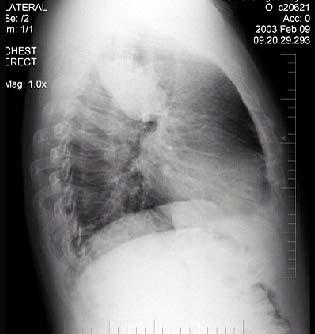

问题 男性,70岁,因胸痛就诊,不咳嗽、发热,X线检查如图,最可能的诊断是 ( )

选项 A.左肺结核瘤 B.左侧叶间积液 C.左肺癌 D.左肺炎性假瘤 E.支气管扩张

答案 C